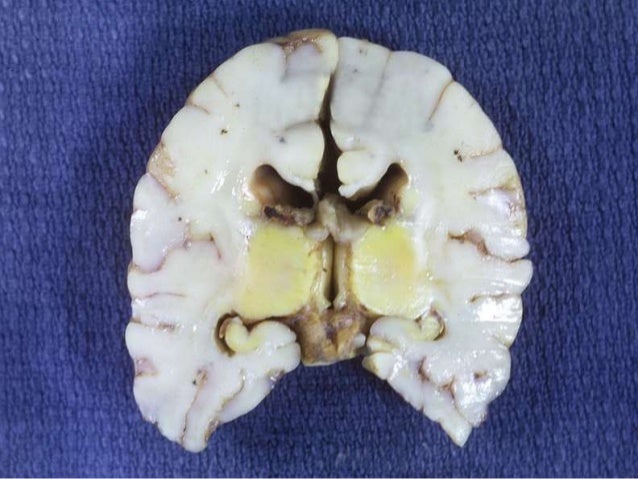

What is yellow staining in kernicterus?

Original autopsy studies of kernicterus identified yellow staining and necrosis of the basal ganglia, specifically in the globus pallidus, indicative of “unbound bilirubin” crossing the blood–brain barrier (BBB). Other regions noted to have cellular damage after hyperbilirubinemia include the substantia nigra reticulata, subthalamic nuclei, vestibular and oculomotor nuclei, hippocampus, and cerebellar Purkinje cells. Loss of neurons, decreased myelination, and gliosis can be observed in the internal and external globus pallidus and subthalamic nuclei. These regions all have functions related to movement, balance, and posture regulation and appear to be selectively vulnerable. The globus pallidus may also serve to integrate inputs from multiple systems including somatosensory and motor pathways; thus, integration of this information may be damaged in patients with kernicterus 17). By contrast, regions such as the striatum and thalamus generally appear to be spared following hyperbilirubinemia. This specific pattern of brain injury helps distinguish bilirubin-induced neurologic dysfunction from injury following hypoxic–ischemia, in which the caudate, putamen, posterior limb of the internal capsule, and cortex are more vulnerable. One theory for the selective vulnerability of the globus pallidus and subthalamic nuclei is their relatively high resting levels of neuronal activity observed in the neonatal brain, compared to nearby regions. Johnston et al. 18) observed that regions with higher neuronal activity are more vulnerable to oxidative stressors or toxins such as bilirubin. Lesions in these regions are observed in infants with classic athetotic cerebral palsy. One hypothesis for the connection between globus pallidus injury and athetosis is that reduced activity of the globus pallidus results in decreased inhibitory input to the thalamus, resulting in its “dys-inhibition” and increased motor activity, consistent with athetosis 19).

Kernicterus refers to the yellow staining of the deep nuclei (i.e., the kernel) of the brain namely, the basal ganglia. Kernicterus involves a specific part of the basal ganglia, the globus pallidus. It also includes lesions (damage) to brainstem nuclei in auditory (hearing), oculomotor (eye movement), and vestibular (balance) ...